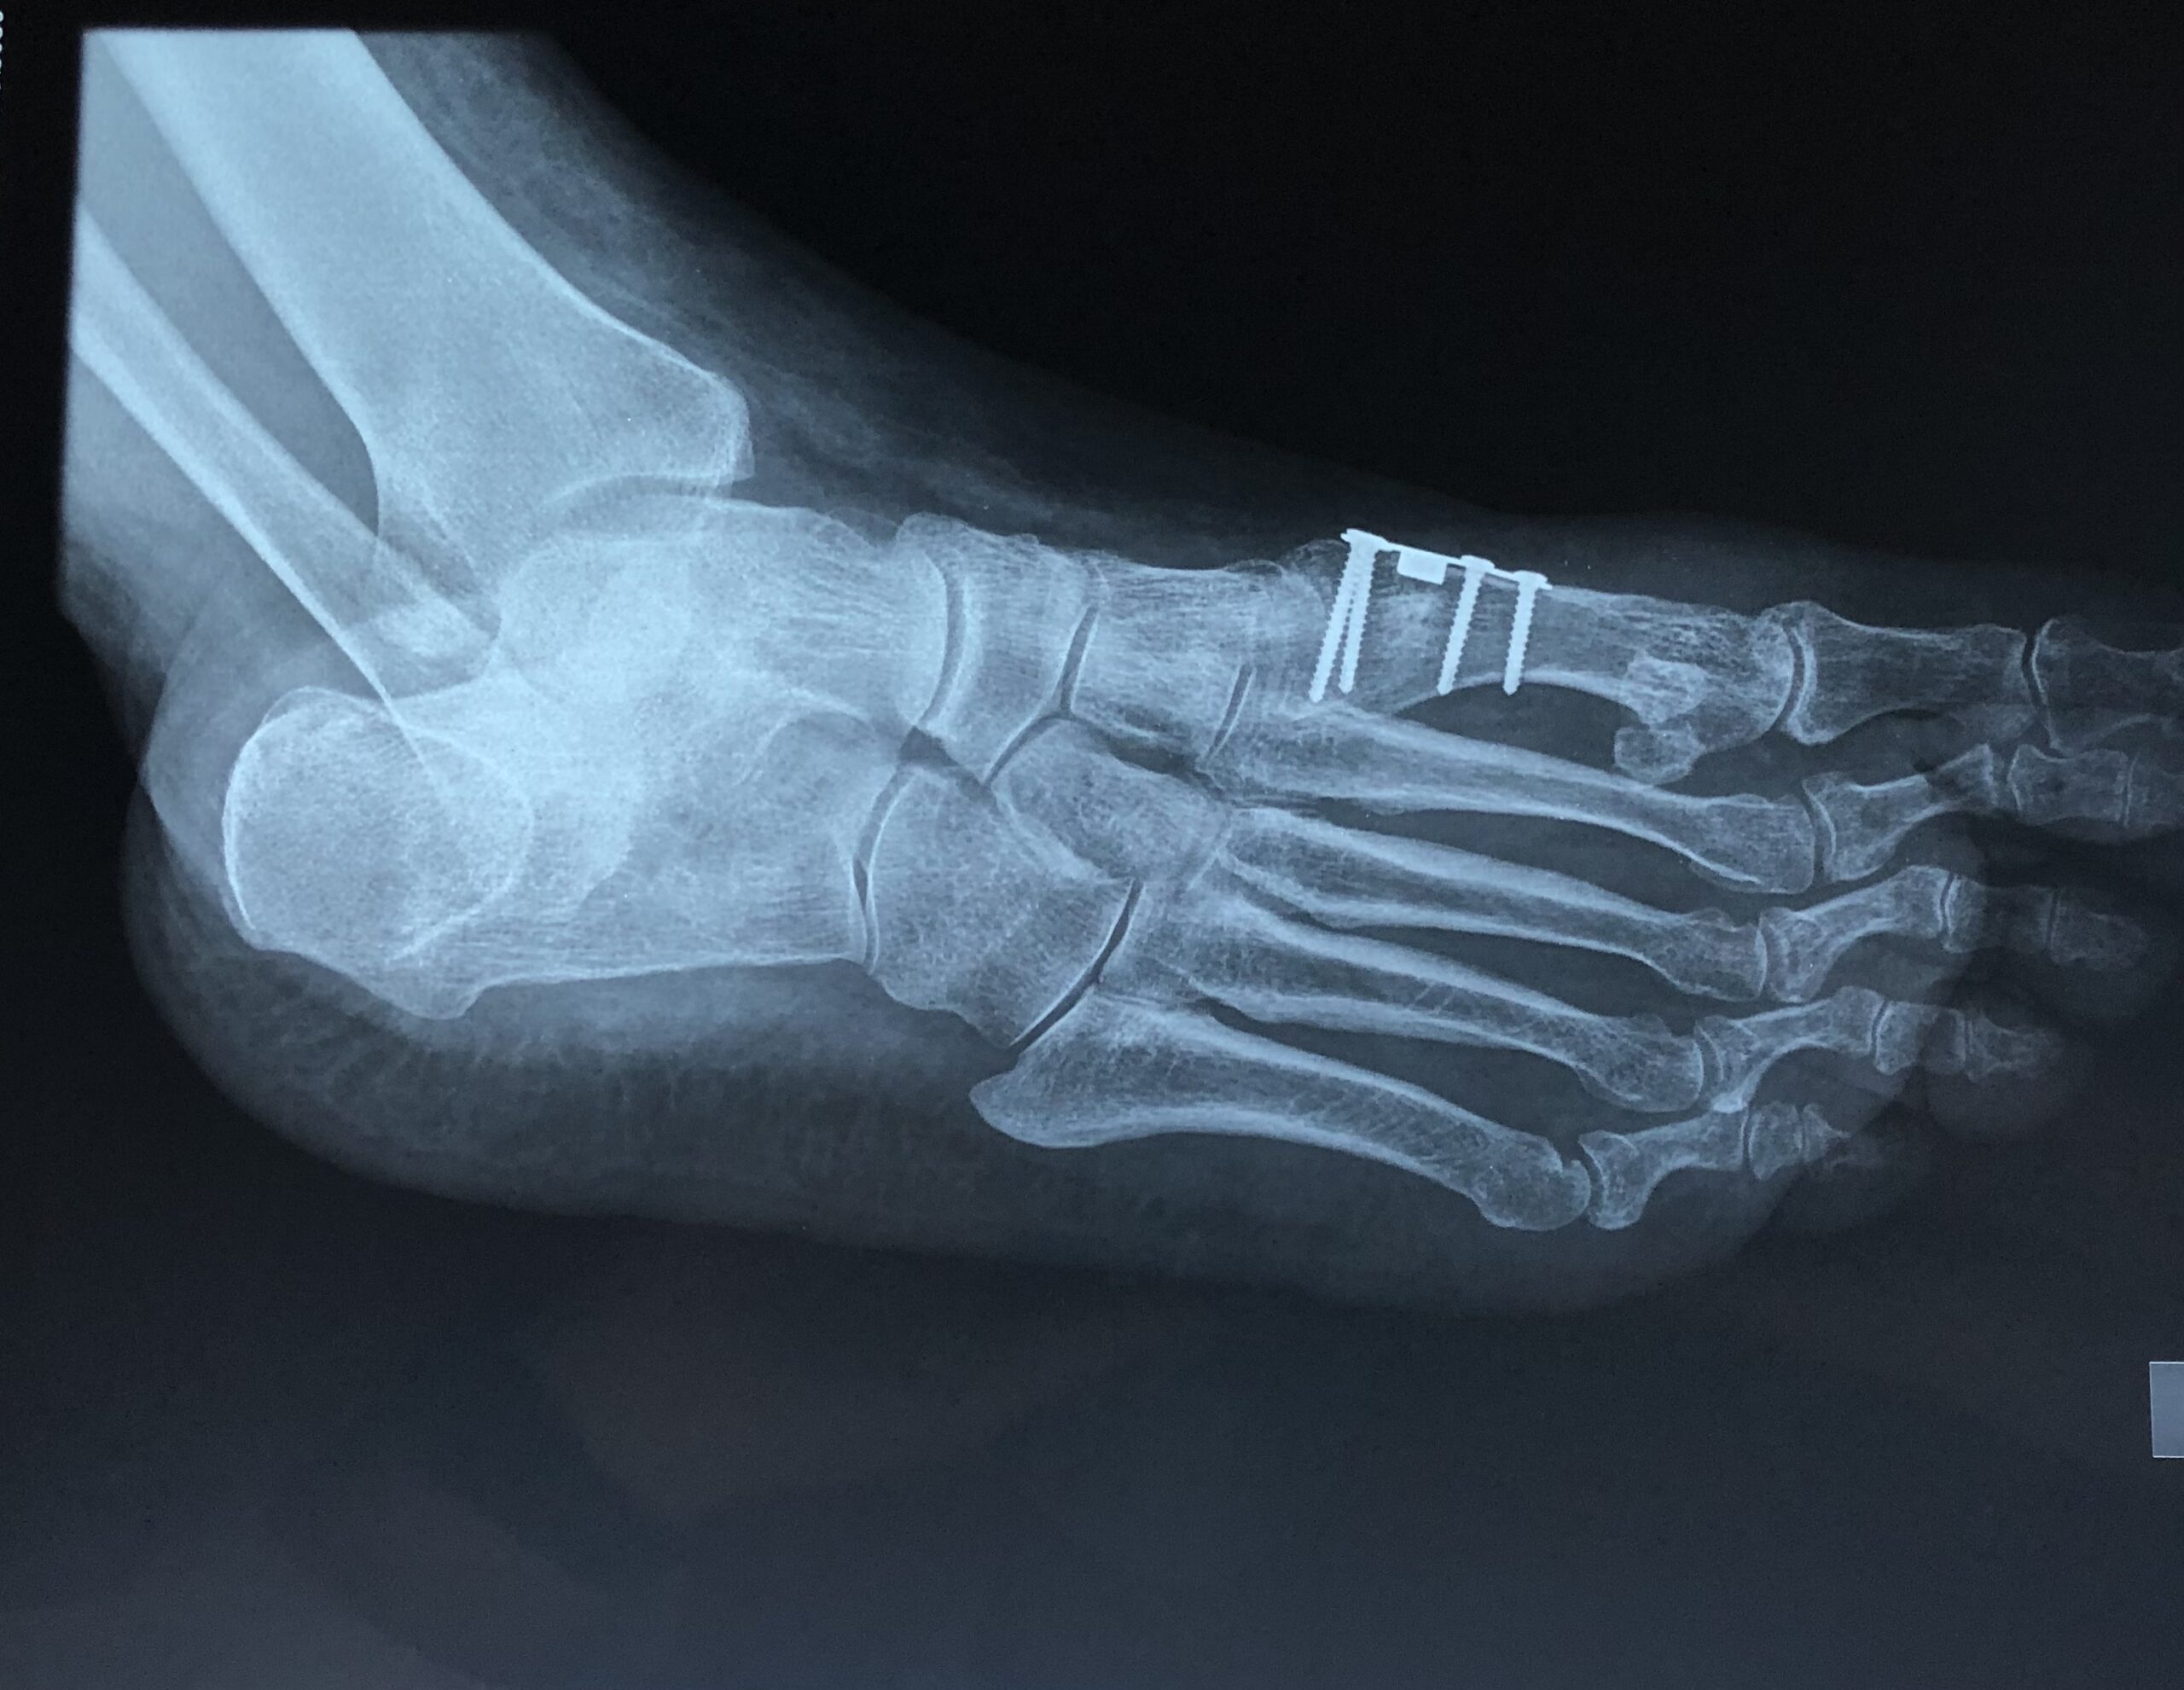

Έχουν περιγραφεί στην διεθνή βιβλιογραφία πάνω από 130 διαφορετικές χειρουργικές τεχνικές για την διόρθωση του βλαισού μεγάλου δακτύλου. Περιλαμβάνουν επεμβάσεις στα μαλακά μόρια της άρθρωσης (θύλακος, σύνδεσμοι, τένοντες) και στα οστά με διενέργεια διορθωτικών οστεοτομιών (σε διαφορα επίπεδα του πρώτου μεταταρσίου και της εγγύς φάλαγγας του μεγάλου δακτύλου). Η χρήση της πιο κατάλληλης τεχνικής και ο συνδυασμός αυτών καθορίζεται από τον βαθμό της παραμόρφωσης, από την ακτινολογικά της χαρακτηριστικά, αλλά και από τις δραστηριότητες του ασθενούς.

Οι επεμβάσεις πραγματοποιούνται με γενική ή περιοχική αναισθησία και ο ασθενήςείναι σε θέση να περπατήσει την ίδια ημέρα με τη χρήση κατάλληλων υποδημάτων χωρίς κάποιο επιπλέον βοήθημα. Σταδιακά επιστρέφει στις καθημερινές του δραστηριότητες, απαλλαγμένος πλήρως από τα συμπτώματα.